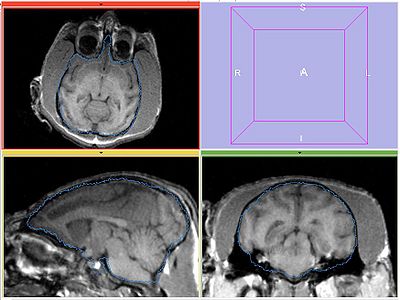

The following screeshots demonstrate good initial alignment of the images with the initial affine transformation, and the outline of ROIs. Also note that FIXED1 and FIXED2 are very similar within ROI.

FIXED1

FIXED2

MOVING (under INITIAL_TFM)